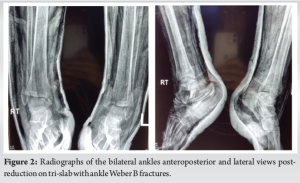

Plain radiographs were done and showed that the patient sustained asymmetrical bimalleolar fractures. On the left, a closed Denis Weber B ankle fracture and Lauge Hansen supination adduction type. On the right, an open Gustilo-Anderson 2, Denis Weber B ankle fracture, and Lauge Hansen supination external rotation type. In the emergency department, the open ankle fracture was irrigated with normal saline, and dressed with wet gauze. Both ankles were reduced under sedation and placed on tri-slabs, and control plain radiographs post-reduction were done (Fig. 2). Stat doses of augmentin 1.2 g intravenous injection and tetanus toxoid 40 IU (0.5 ml) intramuscular and morphine 10 mg were given.